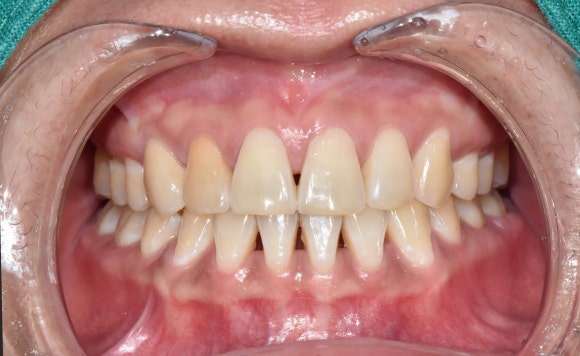

첫번째 케이스

서울재생치과에서 진행한 케이스를 소개드리겠습니다.

오른쪽 앞니를 주의해서 관찰해주세요.

오랜기간 치수괴사를 겪으면서 짙은 오렌지색으로 변색이 일어난 경우에 해당됩니다.

신경치료 후 미백제를 넣고 3회 차에 미백치료를 종료하셨습니다.

(색상 회복이 굉장히 빠르셔서, 몇 번 더 진행하면 옆의 자연치보다 더 하얘질 것 같았습니다^^;)

치료 전 후